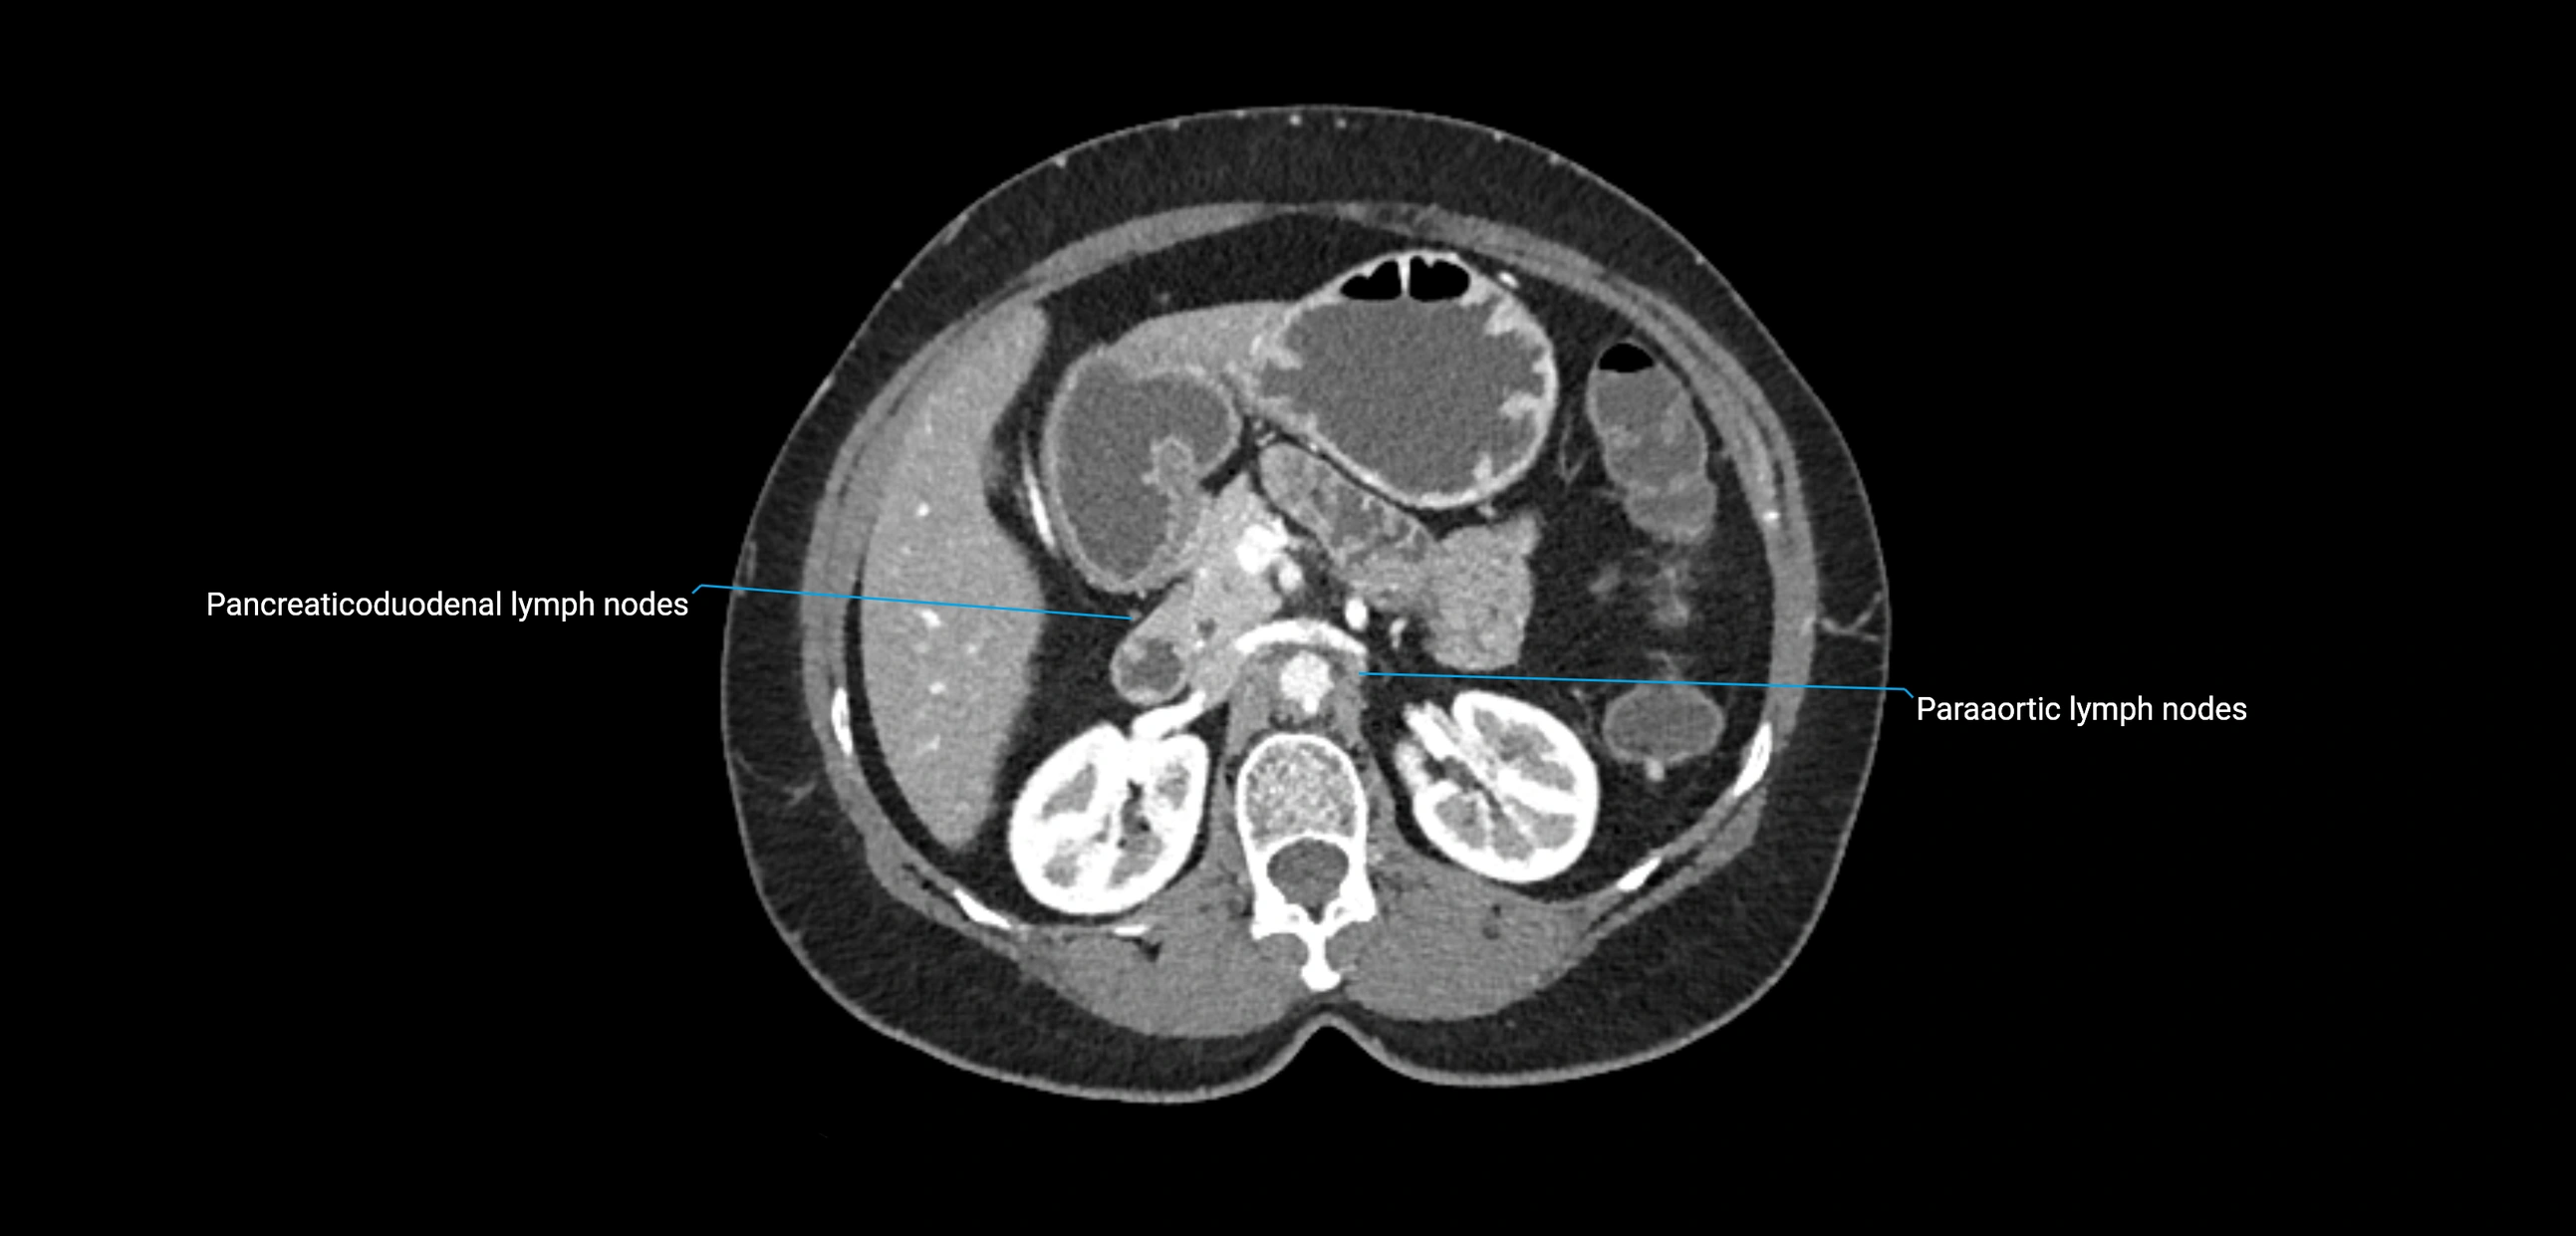

CT Appearance

CT Pre-Contrast:

• Nodes appear as soft-tissue density nodules adjacent to the aorta and IVC

• Calcification may be seen in chronic infections (e.g., tuberculosis)

CT Post-Contrast:

• Normal nodes enhance homogeneously

• Malignant nodes may show heterogeneous enhancement, central necrosis, or conglomerate formation

• Size >1 cm short axis is suspicious, though morphology and distribution are equally important